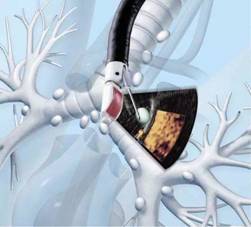

近年来,随着肺部CT检查在临床上的普及,肺外周病变、肺结节发现率明显增加,很多人的第一反应是“我是不是得了肺肿瘤?”,对于一些位于气管或支气管外的病变是常规支气管镜检查的“盲区”,因为常规气管镜只能看到位于气管、支气管内的病变,而对管外的病变常常无能为力。如何精准、高效、安全明确的诊断,又可降低对患者的损伤,这时超声支气管镜(EBUS)技术诞生了!

超声支气管又称支气管内超声,简单的说就是在支气管镜的前端安上了一个超声探头,是一个同时拥有超声和支气管镜两大功能的结合体。今年我院斥巨资购买了这套设备,成为温州南片首家拥有这套设备的医院,同时也填补了我院这项检查技术的空白。目前我院呼吸科高年资医生已熟练掌握该设备的各项用途,也取得了良好的临床效果。

超声支气管镜又细分为EBUS-TBNA(超声支气管镜引导下的经支气管针吸活检术)及EBUS-GS(结合引导鞘的超声支气管镜)。

01 EBUS-TBNA——彩超直视下获取病变组织:

超声支气管镜可清楚显示气管周围病变大小、血供、与周围血管关系

是用超声支气管镜或微型超声探头通过支气管镜送入气管、支气管管腔,通过实时超声扫描,让医师充分了解气管支气管管壁层次的组织学特征及周围邻近脏器的超声图像,从而进一步提高肺部及纵隔病变的诊断水平。